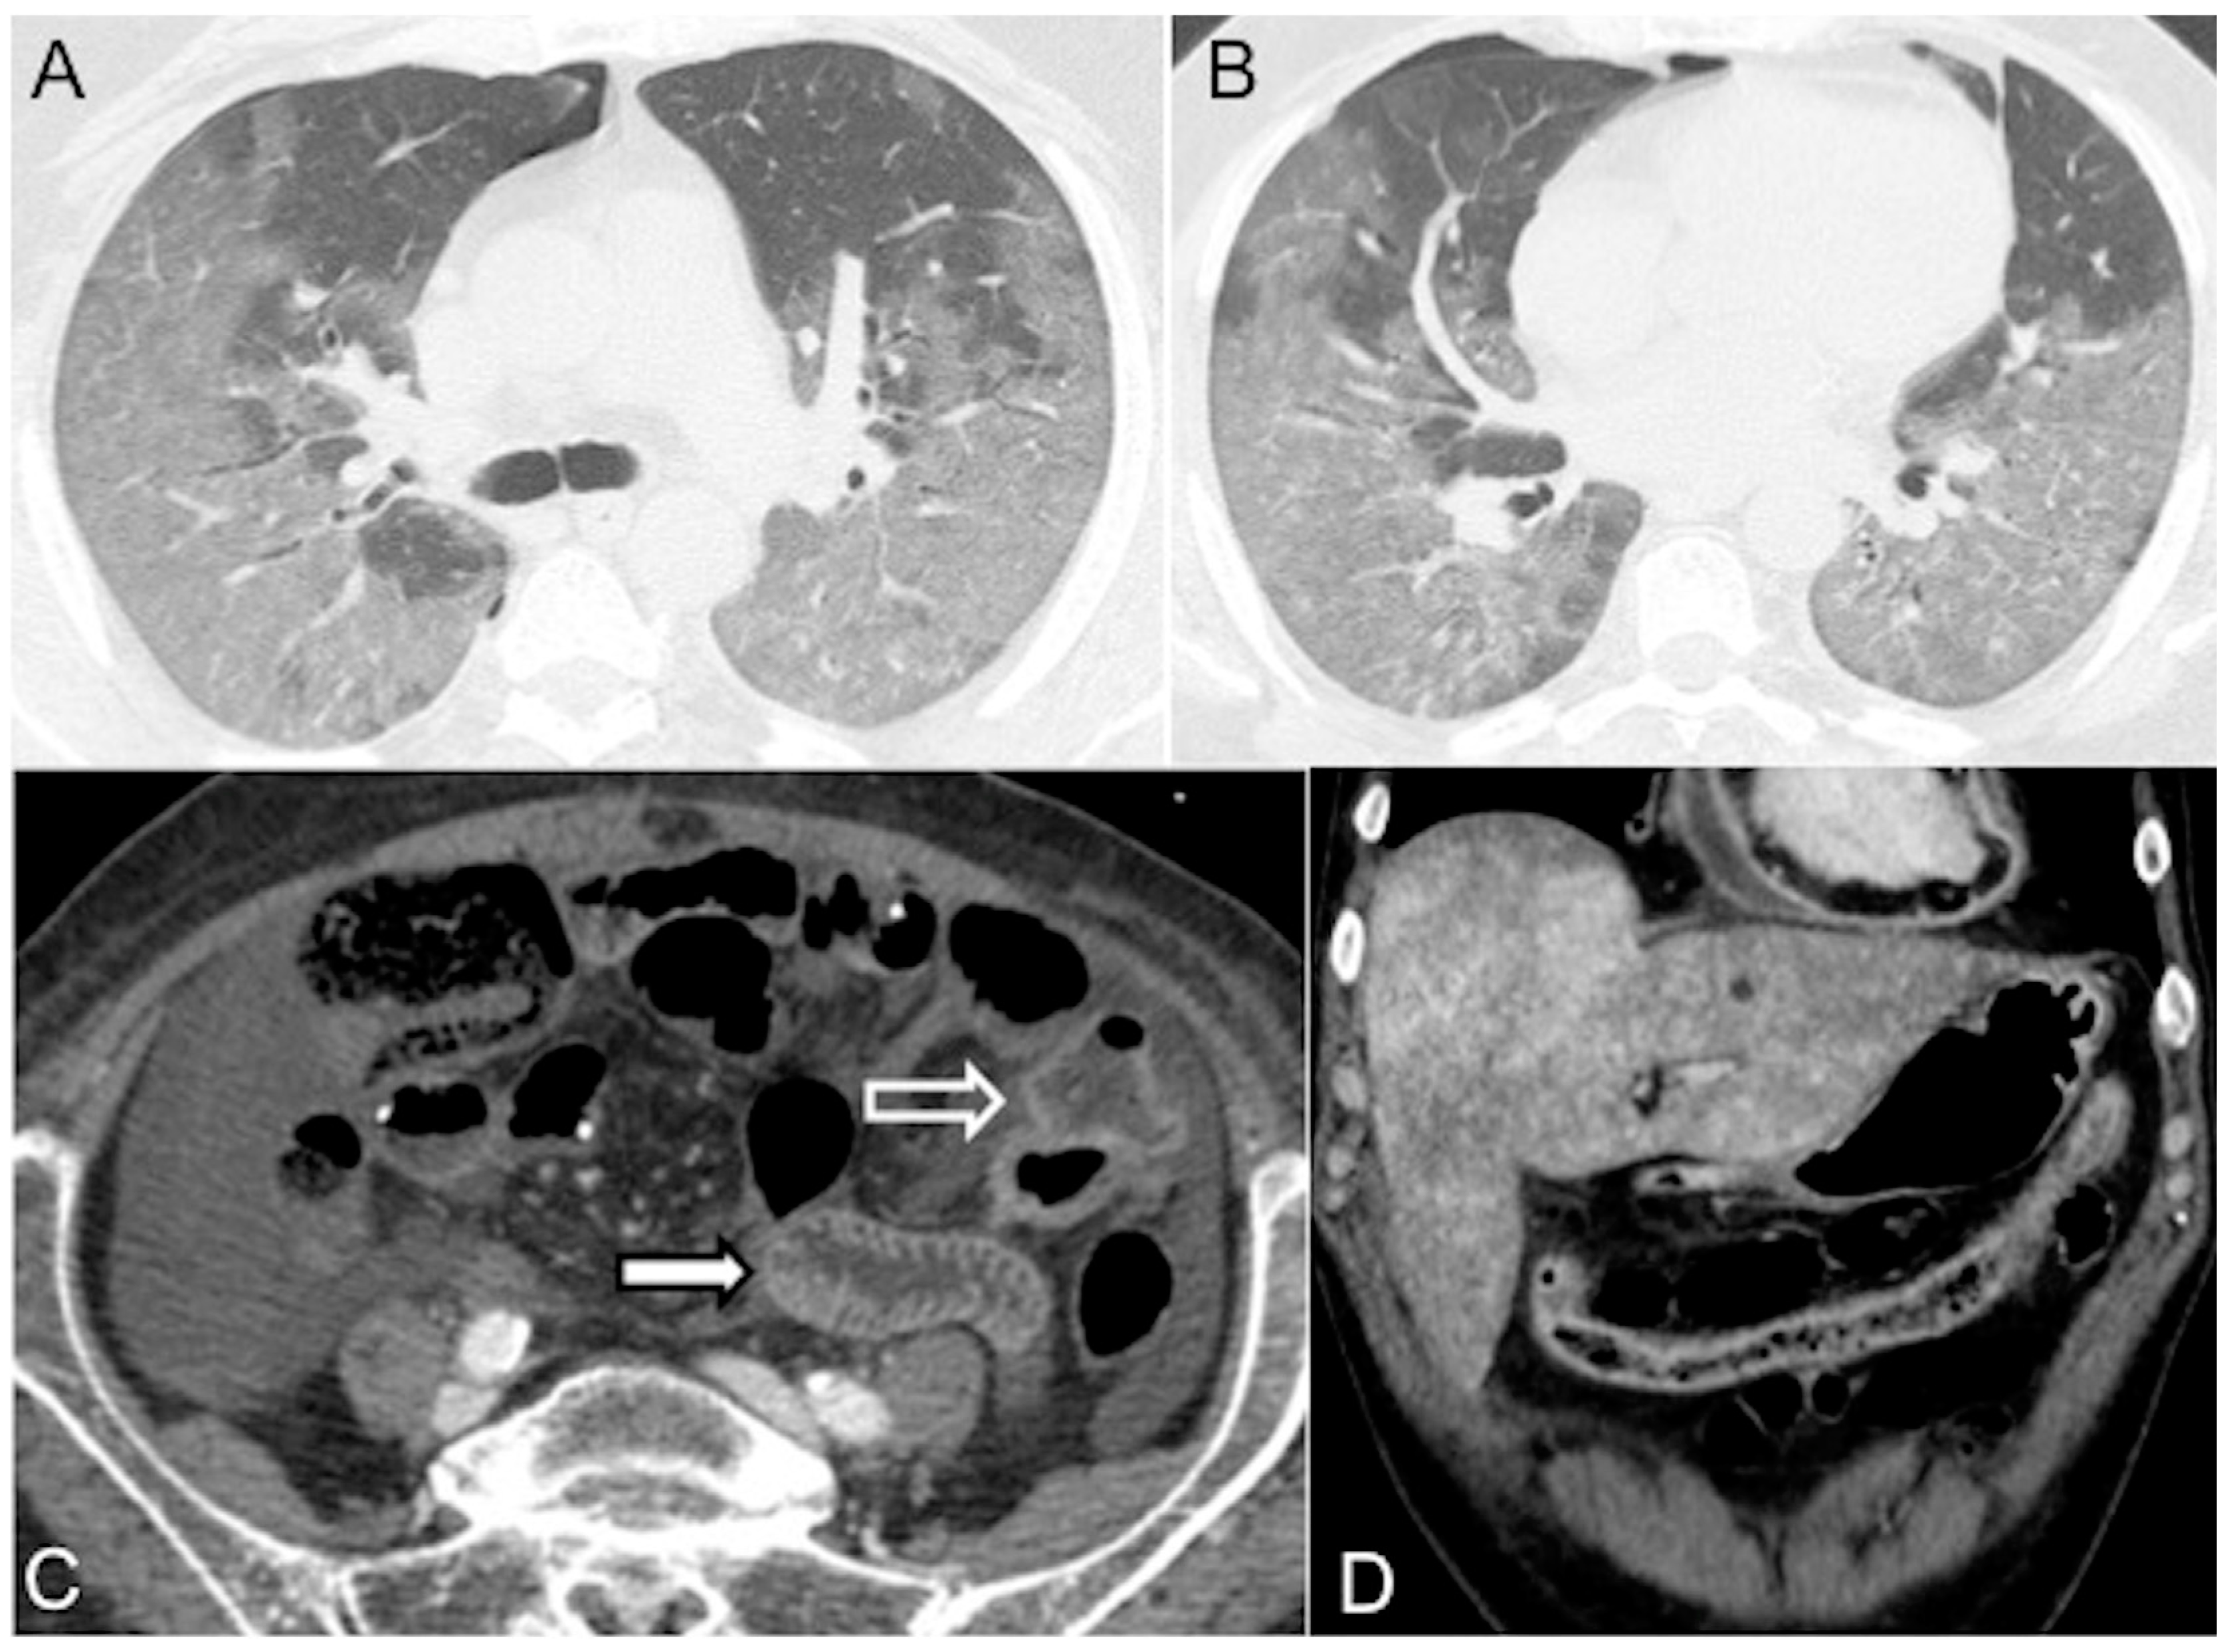

- In irreversible end-organ dysfunction, injected IV CM circulation is supported only by the pressure applied by the automated power injector and the density of contrast material. Circulatory arrest leads to dense contrast pooling and layering in the SVC, IVC (inferior vena cava), and right heart chambers with non-opacified left heart chambers or arterial vessels (Figure 1) [43,45,49,50,51,52]. This may be called the “non-beating heart” pattern. Cardio-pulmonary aggressive resuscitation must immediately be initiated within the framework of a predetermined emergency plan.

- There is the presence of a slit-like or flat inferior vena cava (FIVC) (Figure 2A). This is characterized by an anterior-posterior diameter of less than 9 mm in three consecutive segments, 20 mm above and below the renal veins, and at the level of the perihepatic region. Additionally, a transverse-to-anteroposterior ratio of ≥2.5 at the level of the suprarenal IVC can indicate flattening. The flatness index or IVC diameter ratio is calculated by dividing the maximal transverse and anteroposterior diameters of the IVC [15,16,17,18,19,20,21,22,23,24,25,26,27,28,29,30,31,32,57,58,59,60,61].

- Flattening of the IVC (slit sign) is often seen in cases of decreased circulating blood volume (hypovolemia) and indicates reduced venous return in patients with systemic hypotension. However, it may not be easily appreciated due to the administration of large volumes of fluids [31]. This finding is more commonly observed in acute hypovolemic traumatic patients. Variations in intra-abdominal pressure and the respiratory cycle can also affect the diameter of the IVC. IVC flattening has a specificity of 90% and a sensitivity of 84% in identifying hypo-perfusion shock in spontaneously breathing patients [15,16,17,18,19,20,21,22,23,24,25,26,27,28,29,30,31,32,57,58,59,60,61,62,63]. The IVC diameter ratio measured via CT scans can help predict in-hospital mortality in septic shock patients, with a cut-off value of ≥1.3 cm having 75% sensitivity and 42% specificity [63]. It is also useful in determining the amount of blood transfusion required and assessing the volume status of patients with blunt torso trauma. [64].

- The IVC halo sign is characterized by a low attenuation band (<20 HU) encircling the collapsed intra- and retrohepatic inferior vena cava. This band is caused by a ring or rim of edema [65,66,67]. In cases of severe hypovolemia, approximately 80% of patients may exhibit this sign, resulting from the loss of precapillary arteriolar sphincter tone and the accumulation of fluid surrounding the IVC (Figure 2B–D) [18,25,30,31,65,66,67]. However, it is important to note that this sign is not specific to non-traumatic patients and can also be observed in conditions such as liver congestion, biliary cirrhosis, hepatitis, or other diseases that obstruct lymphatic drainage at the porta hepatis [25].